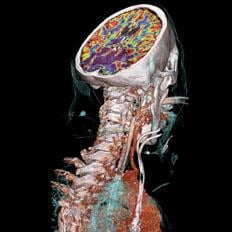

November 11, 2009 – In a collaborative study between ContextVision AB, Massachusetts General Hospital (MGH), the Center for Medical Image Science and Visualization (CMIV) and SharpView AB, researchers will investigate advanced 3D image filtering as a means of increasing patient throughput and improving image quality in MRI and further enabling dose reduction in CT.